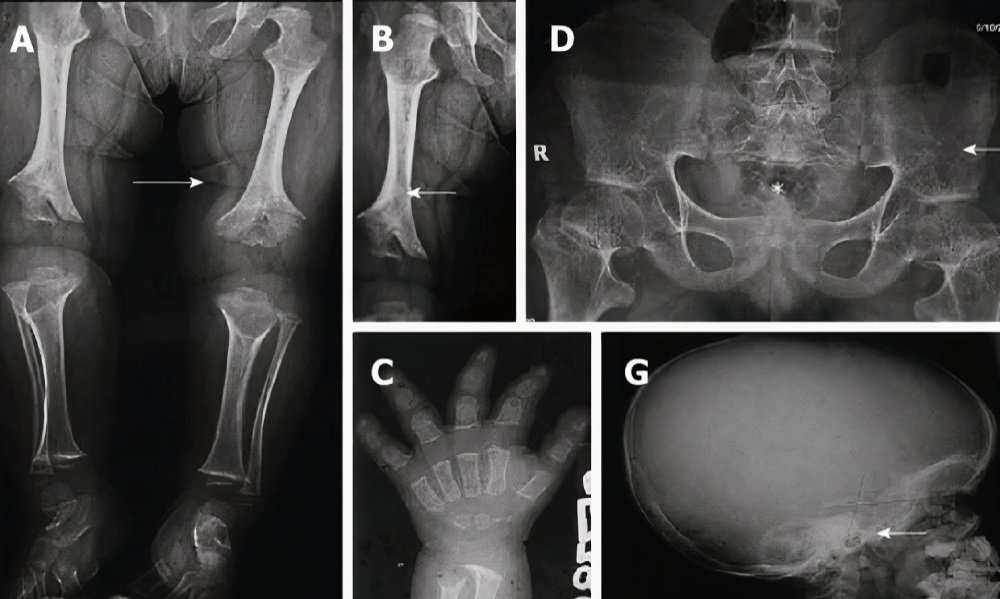

B) Radiological findings include:

- Short ribs with cupped anterior points

- Broad hand with short metacarpals and phalanges, and a trident position

- Fibular overgrowth

- Short and dense tubular bones with metaphyseal cupping, flaring, and irregular growth services

- Small and squared iliac wings with a narrow sciatic notch and parallel acetabular roof

- Congenital narrowing of the spinal canal (spinal stenosis)

- Short and depressed vertebral bodies with nearly large intervertebral disk height

- Broad skull with a narrow foramen magnum and comparatively diminutive skull base

A skeletal overlook is valuable to confirm the diagnosis of achondroplasia.